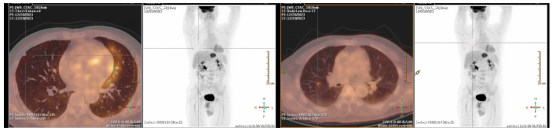

2025.04 PET-CT提示右肺转移瘤较前增大。

image.png

图13 影像评估提示右肺转移瘤较前增大